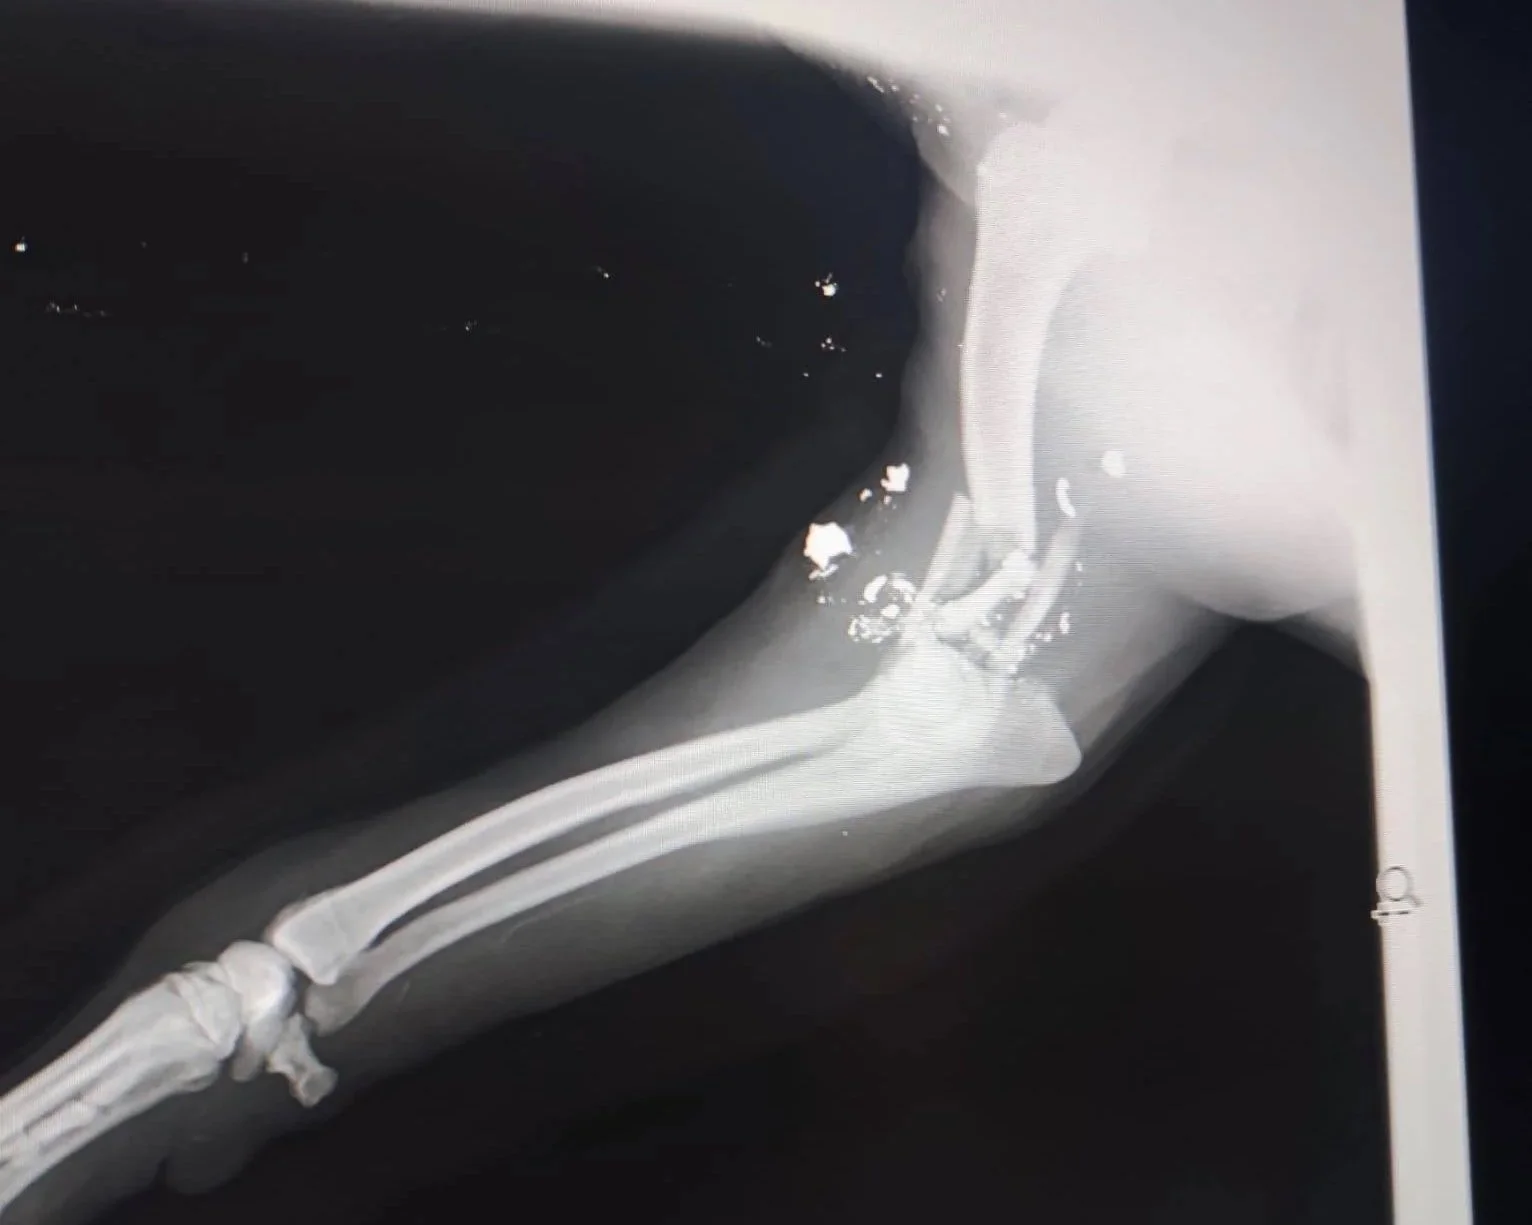

Denuevo nos volvemos a encontrar con otro caso estremecedor.. este pequeño fue encontrado con un disparo con orificio de entrada y salida en su pata que le ha destrozado el hueso. Después de revisiones veterinarias parece inviable la operación para su recuperación.

Está en el Refugio con antiinflamatorios y antibióticos en unos días tiene que volver a revisión.